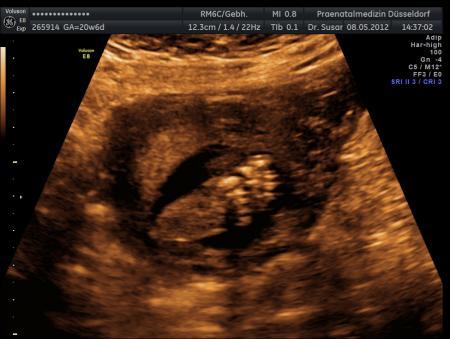

Und aller guten Dinge sind drei :P

Bild zu